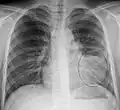

AP CXR showing left lower lobe pneumonia associated with a small left sided pleural effusion -

AP CXR showing right lower lobe pneumonia -

AP CXR showing pneumonia of the lingula of the left lung -